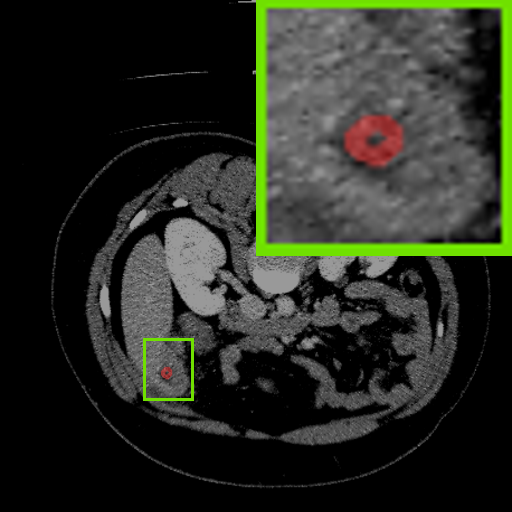

Figure 3: Qualitative comparison visualization of DEAP-3DSAM and baselines on four datasets.

IV-B2 Qualitative Performance Comparison

We also performed qualitative analysis on four datasets. As illustrated in Fig. 3, DEAP-3DSAM accurately identifies the target regions and closely matches their size. In contrast, 3DSAM-Adapter [3dsamadapter] exhibits limitations in matching the size and shape of the target regions. This proves that DEAP-3DSAM captures more complex image features, owing to its Dual Attention Prompter and Feature Enhanced Decoder. Furthermore, while these SAM-based methods are nearly capable of localizing the target regions, many traditional methods, i.e. UNETR++ [unetr++], Swin-UNETR [swinunetr], and TransBTS [transbts], struggle to achieve this. This highlights the potential of SAM-based methods for addressing complex 3D segmentation tasks.